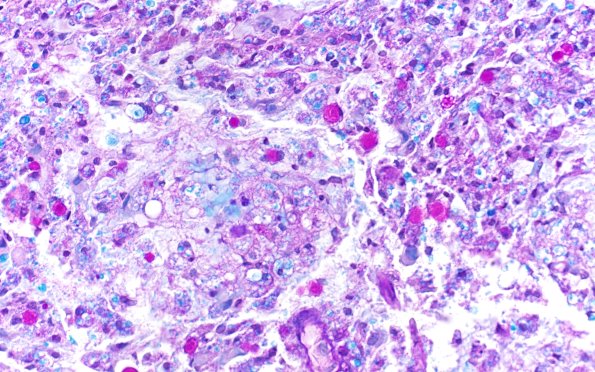

Washington University Experience | MYELIN (IMMUNE-MEDIATED) | Inflammatory Demyelination | 17C3 Demyelination, inflammatory (Case 17) LFB-PAS 40X 1

Small globules and fragments of bright blue myelin debris are present within phagosomes inside macrophages. (LFB-PAS)